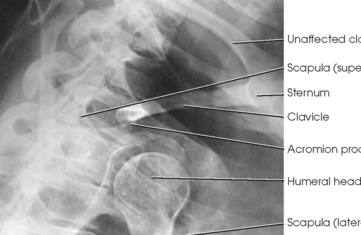

Structures shown: A lateral image of the shoulder and proximal humerus is projected through the thorax (Figs. 5-25 and 5-26).

RAFERT ET AL.1 MODIFICATION